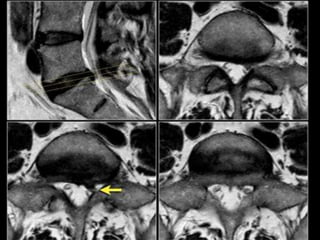

INVESTIGATIONS

MRI

• Clearly superior in the detection of disc

degeneration.

• Allow evaluation of complete spinal group

• Shows:

• Intervertebral disc protrusion.

• Compression of nerve root